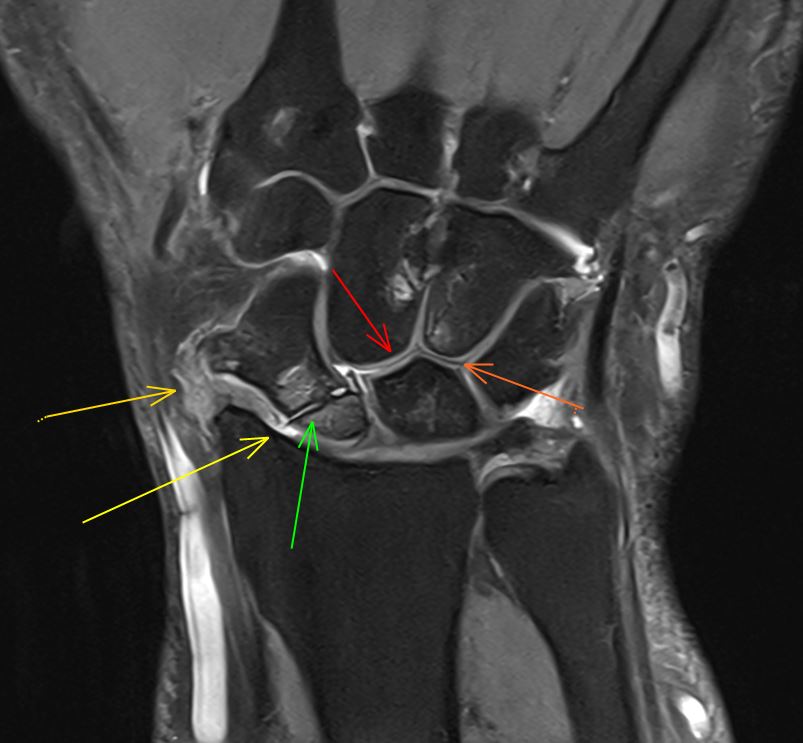

10/7/2024. 🟧💁 Male 28 years-old with longstanding pain after trauma in his right wrist 🤚, years ago. A #MRI is performed. Some features are pointed with different arrows. What´s your diagnosis? The result is coming soon. Stay tunned. #MSK #wristpain #traumatwitter

10/7/2024. 🟧💁 Male 28 years-old with longstanding pain after trauma in his right wrist 🤚, years ago.

A #MRI is performed.

Some features are pointed with different arrows.

What´s your diagnosis?

The result is coming soon. Stay tunned.

#MSK #wristpain #traumatwitter